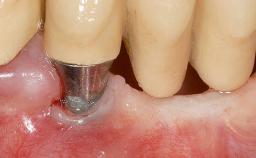

Early Implant Placement, Contour Augmentation, and Autologous Connective-Tissue Graft Using a Tunneling Technique to Replace an Upper Incisor with Generalized Gingival Recession

Variations in soft-tissue volume, evidenced either by an overabundance (Evian and coworkers 1993; Levine and McGuire1997; Dolt and Robbins 1997) or by a deficiency of soft or hard tissue can complicate implant-supported rehabilitations in the esthetic zone (Lorenzana 2008; Lorenzana and coworkers 2009). The present case illustrates the replacement of a failing upper left lateral incisor complicated by generalized severe gingival recession in the esthetic zone.

| Soft Tissue Grafting | Simultaneous |

| Abutment Type | CAD/CAM |